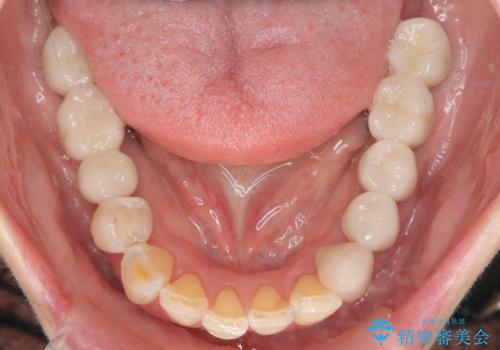

全顎 虫歯 インプラント治療

- 長年悩んでいる歯の見た目や欠損を全て治療したい、と希望され来院されました。

不適合やすり減ったクラウンを全て除去し、虫歯を丁寧に除去したのち精密なセラミック治療を行いました。

また失ってしまった奥歯についてはインプラントを用いて噛み合わせを確立する治療方針としました。

しっかりと調整された咬合関係と、見た目の改善に大変喜んでいただくことができました。